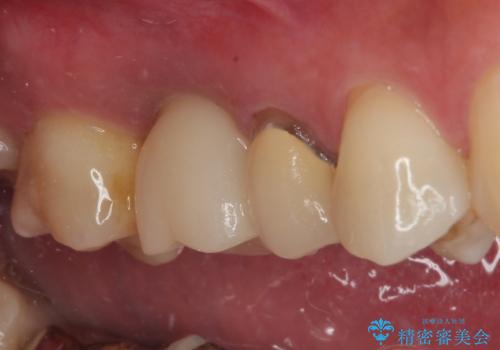

来院されるまではインプラント治療を躊躇されていましたが、抜歯即時埋入により、単回の外科処置で治療が終えられることのメリットを理解され、インプラントによる補綴治療を行いました。

スムーズに治療を終えることができました。